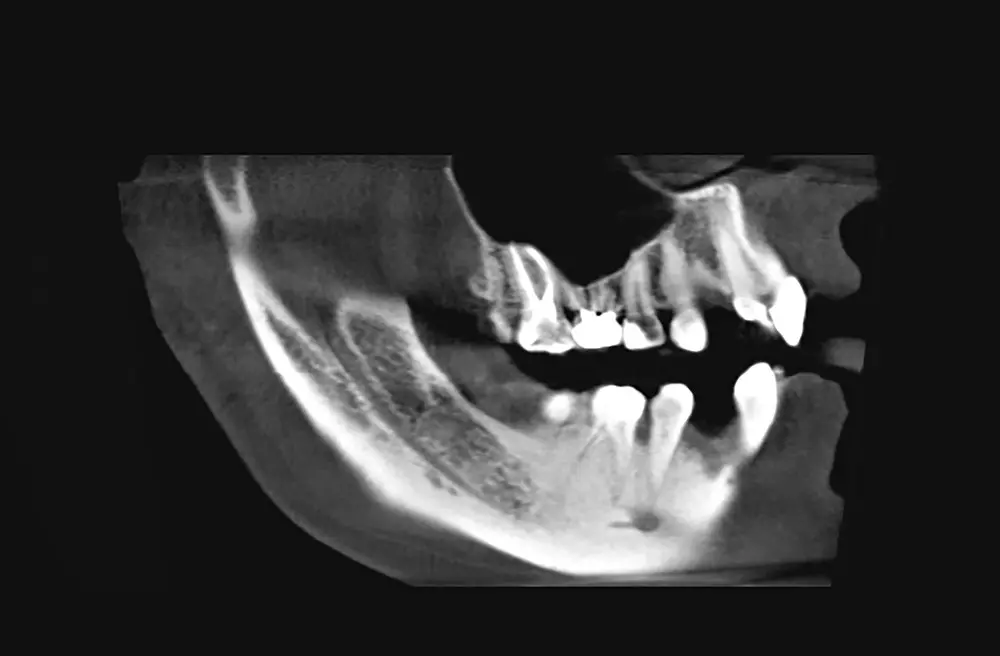

Leczenie kanałowe u dzieci to wciąż temat trudny i budzący wiele wątpliwości wśród stomatologów. Jest tak ze względu na zachowanie najmłodszych, ale i budowę anatomiczną samych mleczaków, których kanały są szerokie i z dużą ilością miazgi, a przy tym bywają zakrzywione, z rozbudowaną deltą wierzchołkową, licznymi kanalikami bocznymi oraz innymi elementami utrudniającymi działanie. Lek. dent. Urszula Matuszak-Suchorska przestrzega stomatologów przed otwieraniem zębów i pozostawieniem ich w tym stanie przez lata, przedstawia wskazania do leczenia kanałowego u dzieci, omawia także pięć przypadków, w których leczenie endodontyczne okazało się konieczne. Zachęcamy do lektury artykułu!